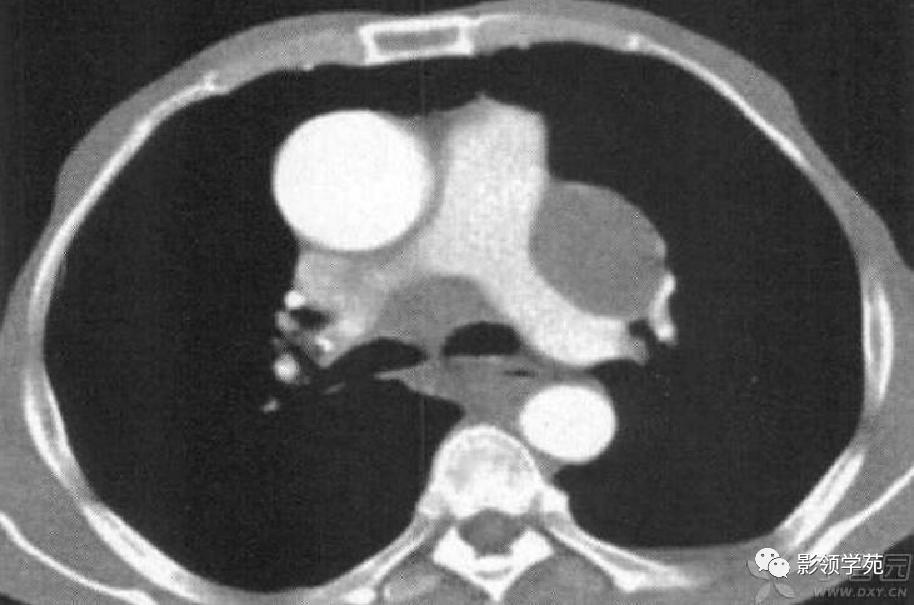

病例1:双肺多发大小不等结节,右肺中叶结节周围见晕轮征及供养血管征。

病例2:右肺下叶肿块周围见晕轮征